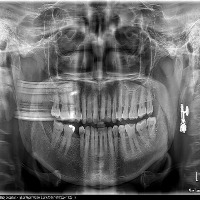

opg12 Computer Vision Project

ask

downloadsClasses (27)

ABCESS

ANKYOLISED TOOTH

ATTRITED TOOTH

BONE LOSS

BROKEN TOOTH

CARIES

CONDYLE

CROWN

CROWN AND BRIDGE

ERUPTING TOOTH

FRACTURE FURCATION INVOLVEMENT

GROSSLY DECAYED TOOTH

HARD PALATE

IMPACTED TOOTH

IMPLANT

INFERIOR ALVEOLAR NERVE CANAL

INFERIOR BORDER OF MANDIBLE

NERVE CANAL

RAMUS OF MANDIBLE

RESTORATION

ROOT CANAL BEYOND APEX

ROOT CANAL TREATED TOOTH

ROOT STUMP

SHORTENED RCT

VERTICAL BONE LOSS

maxillary sinus